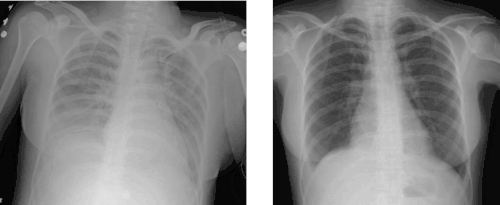

Chest X-ray of transfusion-related acute lung injury (TRALI) compared to chest X-ray of the same person after treatment